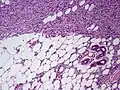

| Histopathological image of dermatofibrosarcoma protuberans. Local recurrence long after the first excision. H&E stain | |

- Subcutaneous tissue infiltration (i.e. "honeycomb" growth pattern)

- Monotonous, plexiform structure of tumour

- DFSP formed both by fibroblastic and histiocytic elements

- Hemosiderin deposits beneath the tumour

- Immunostain positive for CD34